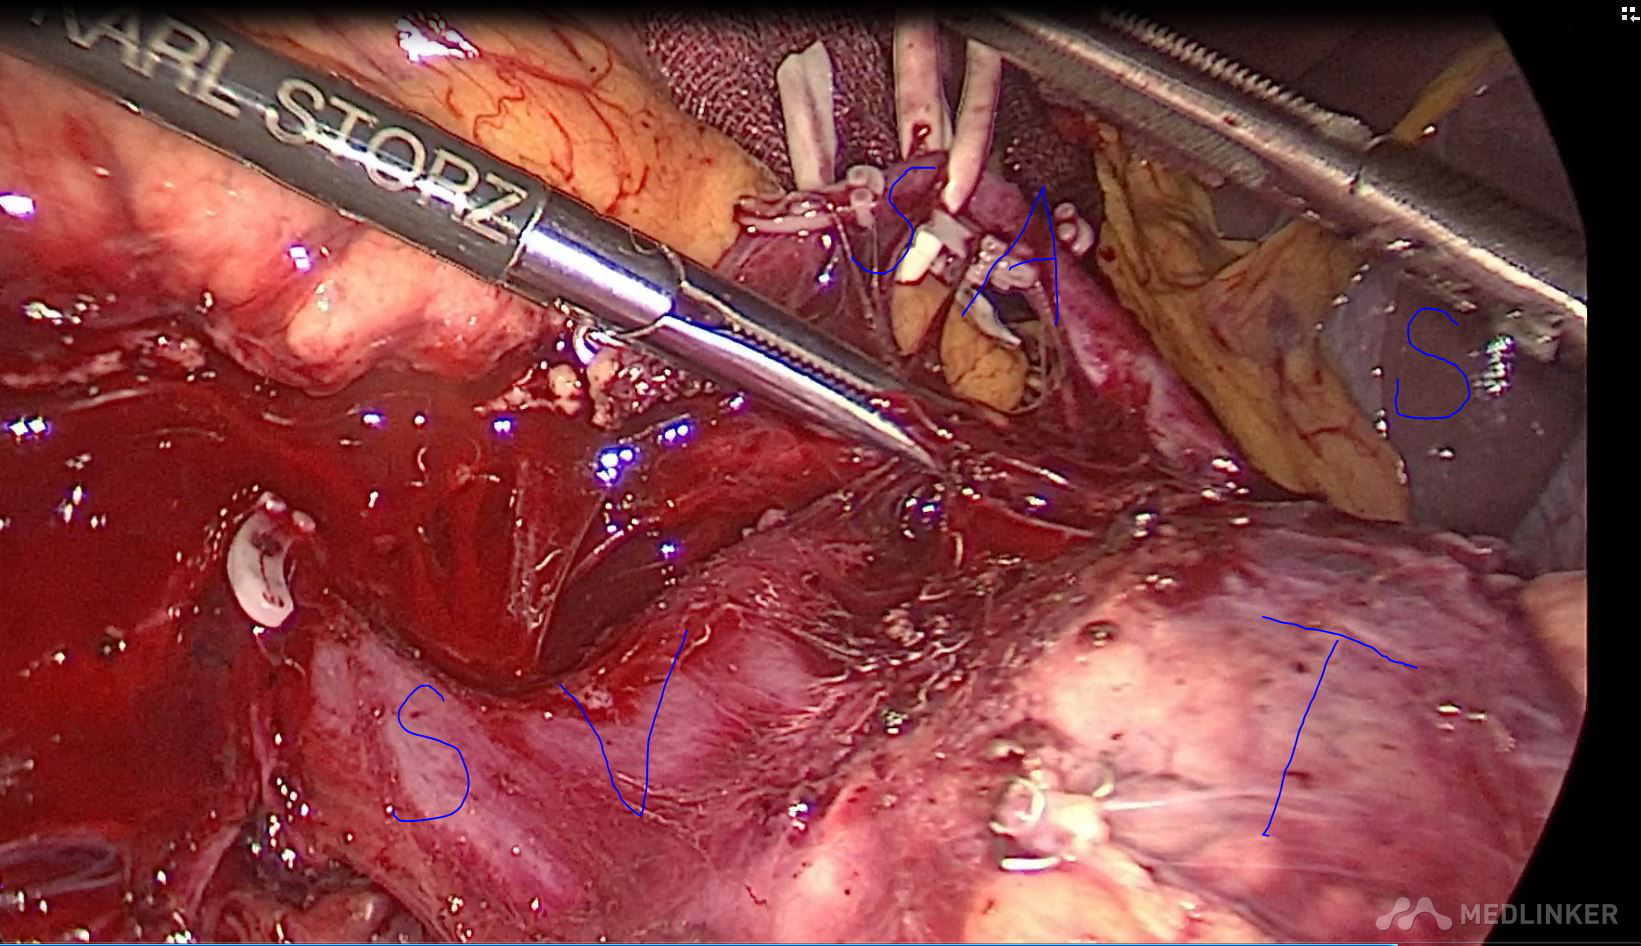

诊断 胰腺囊性肿瘤 囊腺瘤可能性大,术后病理 粘液性囊腺瘤 治疗 全麻下腹腔镜保脾胰体尾切除

术后恢复顺利,没有出现胰瘘。 胰腺粘液性囊腺瘤由于可能恶变,应该早期手术治疗,传统方式一般开腹手术,由于胰体尾与脾脏灌洗密切,经常需要联合脾脏切除。而脾脏除了具有免疫功能,还有滤血,毁血,储血等功能,故保留脾脏对于患者来讲意义肿大。腹腔镜手术由于独特视角以及放大作用,可以做到保脾胰体尾手术,术中尽量保留脾血管(Kimura手术),如果各种原因,脾血管无法保留,此时仍然可以尝试保脾(Warshaw手术),这时脾脏通过胃血管供血,术后功能良好。